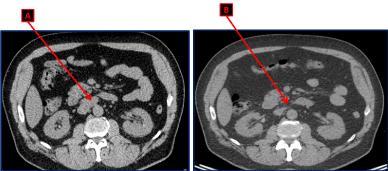

Unfortunately, on the third follow up evaluation and 9 months after the diagnosis, the chest abdomen and pelvis CT scan showed an interval appearance of multiple retroperitoneal supra-centimetric lymphadenopathies: a 2.5×2 cm lymph node (LN) in the liver hilum, a 3.4 x 2 cm magma of LN in the inter aortocaval space and a 1.2 cm LN anteriorly to the inferior vena cava (Figure 1A). However, the bilateral lung nodules, the parenchymal infiltrates associated with the known mediastinal lymphadenopathies secondary to sarcoidosis were stable.

Figure 1. CT scan of the abdomen and pelvis showing the magma of retroperitoneal lymphadenopathies in the aortocaval space (A) upon recurrence. These lymph nodes disappeared after 4 cycles of chemotherapy with Cisplatin and Etoposide (B).

After the fourth cycle, a chest abdomen and pelvic CT scan, an abdominal MRI and a PET CT scan were repeated. The known bilateral lung nodules and mediastinal LN secondary to his well-known sarcoidosis were stable. However, all the retroperitoneal lymphadenopathies that were seen before starting the chemotherapy, have disappeared (Figures 1B and 3). Furthermore, the PET CT scan confirmed the disappearance of the retroperitoneal disease, and revealed a complete metabolic response (Figure 2).